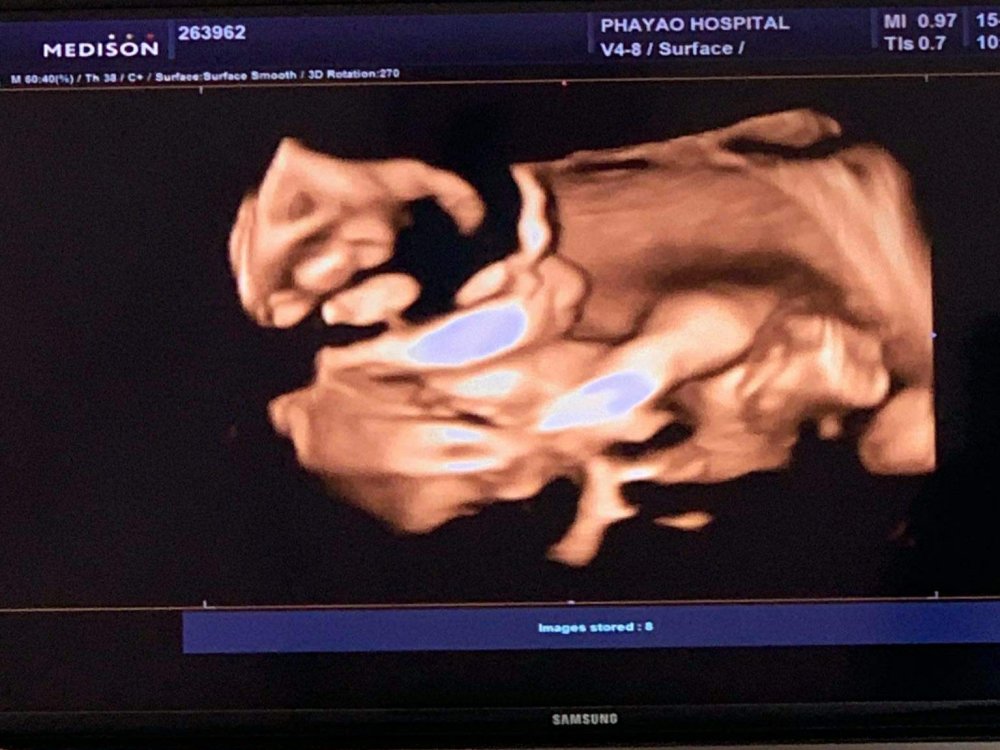

ฝากครรภ์ครั้งนี้ แฟนตั้งใจว่าจะอัลตร้าซาวด์ 4 มิติ เพื่อจะได้เห็นหน้าลูกสาวตัวน้อยเป็นครั้งแรก หลังจากที่เตะท้องแม่อยู่หลายสัปดาห์ โดยการอัลตร้าซาวด์ 4 มิติ นี้ หลักการคือ การถ่ายภาพแล้วนำมาเรียงต่อกันให้เป็นภาพเคลื่อนไหว โดยใช้คลื่นเสียง ซึ่งภาพที่จะปรากฎก็จะเป็นภาพแบบ Real Time ครับ โดยอายุครรภ์ที่เหมาะสม ที่สามารถเริ่มซาวด์ได้ก็ตั้งแต่สัปดาห์ที่ 19 ของการตั้งครรภ์ เป็นต้นไปครับ

ข้อดีของการซาวด์ 4 มิติ คือ จะสามารถเห็นอวัยวะ , เพศลูก , โครงสร้างใบหน้า , กระดูกสันหลัง , พัฒนาการในครรภ์ และอื่น ๆ

แต่ว่าช่วงที่ไปลูกนอนอยู่พอดี จึงขยับตัวน้อย มีหาวบ้าง เอานิ้วมาดูดบ้าง เรียกได้ว่าการมาซาวด์ ก็ต้องอาศัยโชคในระดับหนึ่งเหมือนการซาวด์ปกตินั่นแหละ แต่ได้เห็นเพียงเท่านี้ รู้ว่าลูกร่างกายแข็งแรงสมบูรณ์ ครบ 32 ก็เป็นความสุขของคนเป็นพ่อเป็นแม่แล้วใช่ไหมละครับ